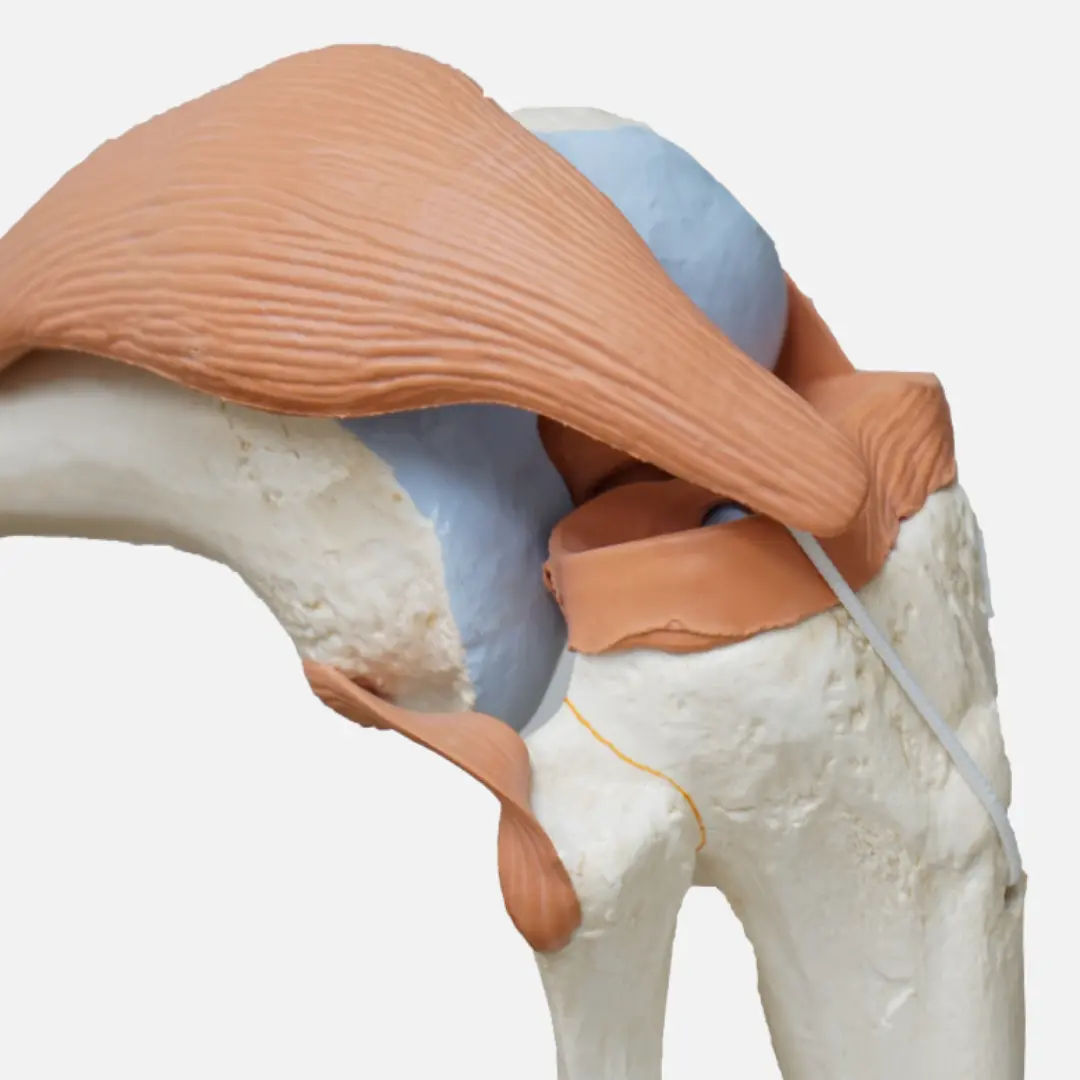

무릎 연골 손상의 치료 방법은 손상 정도와 환자의 상태에 따라 다양하게 결정됩니다. 초기에는 보존적인 치료를 우선적으로 시행할 수 있어요. 여기에는 약물 치료, 물리 치료, 주사 치료 등이 포함됩니다. 약물 치료는 통증과 염증을 완화하기 위해 소염진통제 등을 사용할 수 있습니다. 물리 치료는 근력 강화 운동, 스트레칭, 온찜질 등을 통해 무릎 주변 근육을 강화하고 관절의 움직임을 개선하는 데 도움을 줍니다.

주사 치료는 관절 내에 히알루론산이나 스테로이드 등을 주입하여 통증을 줄이고 관절의 윤활 기능을 회복시키는 방법입니다. 하지만 이러한 보존적인 치료에도 불구하고 증상이 호전되지 않거나, 손상 정도가 심한 경우에는 수술적 치료를 고려할 수 있습니다. 수술 방법에는 관절 내시경을 이용한 연골 봉합술, 절제술, 미세 천공술, 그리고 심한 경우 인공관절 치환술 등이 있습니다. 전문의와 충분히 상담하여 자신의 상태에 가장 적합한 치료 방법을 결정하는 것이 중요합니다.